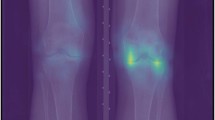

Figure 1 depicts the association of K/L score with knee pain severity. In all five racial/ethnic populations, the severity of ROA, indicated by K/L grade, and the severity of knee pain were positively associated (p for trend < 0.001 for all studies). Compared to knees with no ROA (K/L grade = 0), the odds ratios of the degree of pain severity for knees with mild ROA (K/L grade = 2) were 6.3 (95% CI: 2.7–15.1) among urban Chinese, 5.6 (95% CI: 1.7–18.9) among rural Chinese, 3.0 (95% CI: 0.2–41.3) among Japanese, 8.1 (95% CI: 1.7–38.0) among Koreans, 2.2 (95% CI: 1.0–4.7) among African-Americans, and 3.3 (95% CI: 2.3–4.6) among Caucasians.

Association between radiographic knee OA and knee pain severity in five racial/ethnic populations*. *Amalgamating conditional logistic regression results for subjects with knees discordant for the severity of pain. Abbreviations: BOA, Beijing Osteoarthritis Study, China; WOA, Wuchuan Osteoarthritis Study, China; ROAD, Research on Osteoarthritis/osteoporosis Against Disability Study, Japan; HAS, Hallym Aging Study, South Korea; OAI, Osteoarthritis Initiative, United States; CI, confidence interval; K/L, Kellgren &and Lawrence grade.